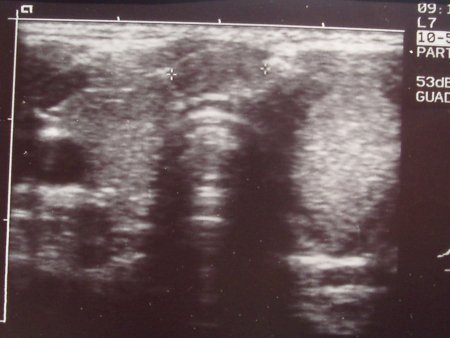

Nel sospetto di una linfoadenopatia reattiva ad una flogosi delle alte vie, dopo aver eseguito un tampone faringeo risultato negativo per SBEA, inizia, in maniera empirica, terapia antibiotica con cefalosporina orale che assume per 10 giorni senza risposta sul quadro clinico. Una nuova valutazione clinica conferma la già nota linfoadenopatia ed una attenta rivalutazione della tiroide evidenzia una modesta pastosità del lobo sin.. Esegue esami ematochimici, compresi gli ormoni tiroidei e la ricerca di anticorpi per infezioni virali, che risultano nella norma. L'ecografia del collo e della tiroide evidenzia un lobo tiroideo sin. quasi interamente occupato da un'estesa formazione di circa 21 mm di diametro (Figura 1 e Figura 2), a profili arrotondati e sfumati, ad ecostruttura solida iperriflettente ed irregolarmente vascolarizzata e la presenza di un linfonodo in sede istmica di circa 8 mm di diametro ed uno in sede laterocervicale sin. di circa 20 mm entrambi ad ecostruttura analoga a quella della formazione presente nel lobo tiroideo di sin.. Esegue agoaspirato con ago sottile che conferma il sospetto diagnostico di neoplasia maligna (CPT).